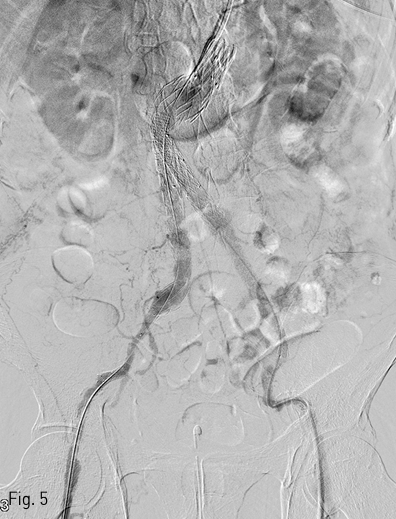

2018년 좌측발의 통증과 색깔변화를 주소로 내원하여 시행한 조영증강 CT(Fig. 1)상에서 발견된 복부대동맥 및 양측 장골 동맥류에 대해 InCraft(Cordis, Milpats, US)를 이용한 EVAR 치료(Fig. 2)를 받은 환자로, 술후 퇴원전 조영증강 CT(Fig. 3)상에서 우측 장골 분지 인조혈관이 폐색된 소견을 보였다.

Fig 1

Pre EVAR CT angiography demonstrates abdominal aortic aneurysm with hostile neck.